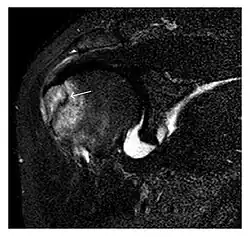

The greater tuberosity of the humerus is also an illustrative location of occult fractures. The osseous injury may follow seizures, glenohumeral dislocation, forced abduction, or direct impaction. They are commonly discovered on MRI in symptomatic patients with suspicion of rotator cuff tear. Coronal images are best suited for detection. They appear as crescentic oblique lines surrounded by a bone marrow edema pattern (Figure 5). The rotator cuff must be inspected since associated ligamentous lesions are common. In the ankle, malleoli and tarsal bones should be checked carefully for any cortical disruptions and radiolucent lines that may reveal a fracture. Awareness of the exact location of the pain will help direct the attention of the interpreter when searching for very subtle signs of fracture (Figure 6).[1]

Figure 7: Fatigue fracture of the talus in a 25-year-old male basketball player with right hind foot and ankle pain, without history of trauma, and a normal initial radiograph (not shown). (a) One-month followup lateral radiograph shows normal appearance. (b) Sagittal T1-weighted MRI shows an irregular fracture line (arrow) within an ill-defined area of hypointensity corresponding to bone marrow edema.[1]